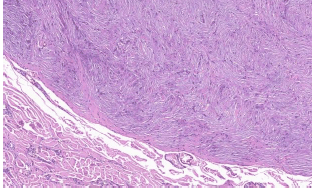

Homem, 25 anos, com nódulo bem delimitado de 1 cm, sem topografia especificada. Recebido fuso de pele com lesão nodular central. Observe a figura abaixo. Assinale a alternativa que apresenta o diagnóstico.